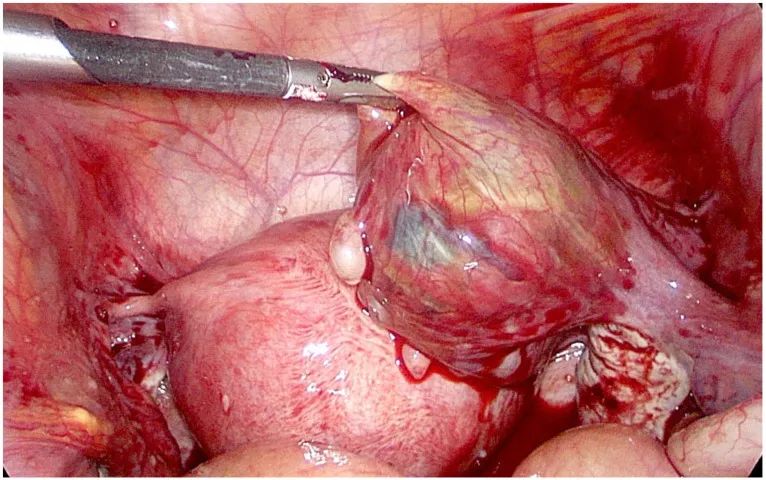

腹腔鏡可見輸卵管壺腹部異位妊娠

然後做了急診手術,切除了輸卵管的異位妊娠。後面順利康復,在39周的時候產下健康嬰兒【1】。